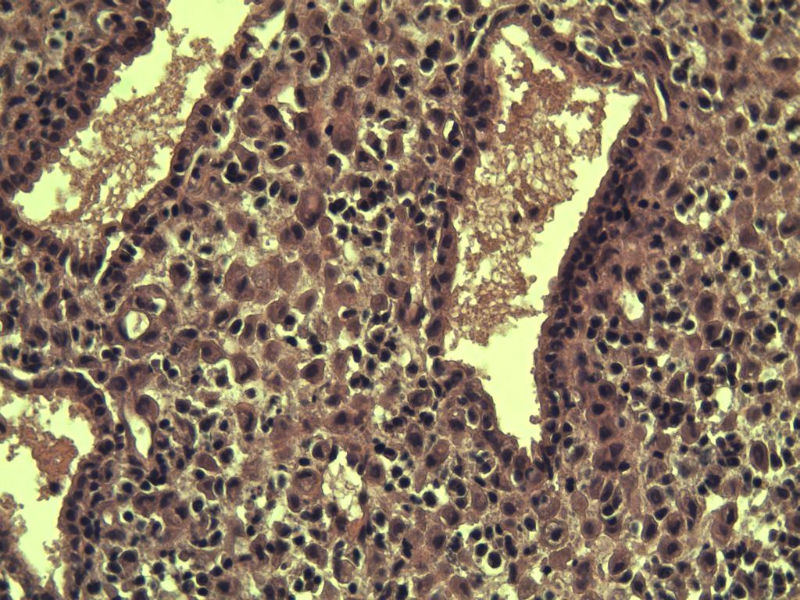

这是另外一个 40岁 经期延长 流血量增多 半年 这是蜕膜样变吧 有什么意义吗? 要报告不?